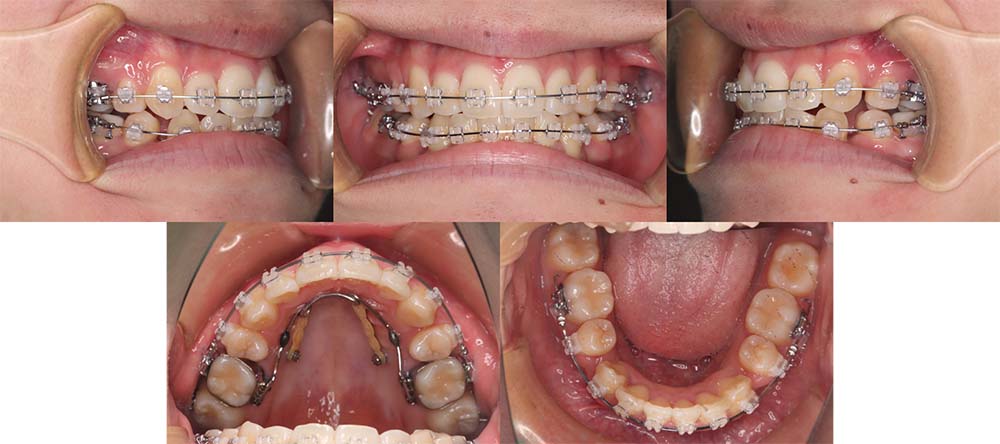

| 症例分類 | 叢生、上顎前突、口唇突出 |

| 診断名 | 下顎重度叢生を伴う骨格性上顎前突 |

| 主訴 | 歯並びが悪い、ものがよく噛めない、口元が気になる、歯科医師に勧められた |

| 年齢 | 22歳10ヶ月 |

| 性別 | 女性 |

| 抜歯部位 | 上下左右の第一小臼歯(4本) |

| 使用装置 | 表側のワイヤー装置 |

| 治療期間 | 2年2ヶ月 |

| 保定装置 | 固定式保定装置、取り外し式保定装置(8時間) |

| 費用 |

[検査・診断料] ¥49,500 [基本施術料] ¥792,000 [調整料] ¥4,400/回 [抜歯] ¥5,500/本 [保定装置] ¥55,000(税込) 抜歯や虫歯治療は他院にて費用が別途かかります。(抜歯¥4,000〜10,000/本)

下顎前歯重度叢生と上顎歯列の前方位、口唇閉鎖不全、口唇突出感があるため、上顎両側第一小臼歯と下顎両側第一小臼歯を抜去して治療を行いました。上顎前歯をしっかりと舌側移動しないといけなかったため矯正用アンカースクリューを使用しました。

前歯がしっかりと舌側移動できたため、口唇閉鎖不全が改善され口唇突出感もなくなり、問題なく咬合させることができました。